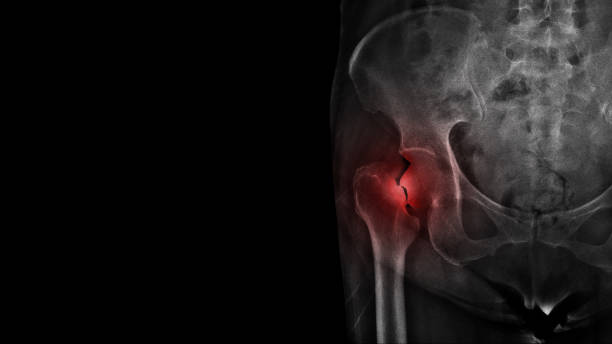

고관절 수술후 회복기간- 수술 후 1주일: 치료와 통증 관리

수술 후 1주일은 가장 중요한 시기입니다. 이 때에는 처음 수술에 대한 통증이 가장 심하며, 치료와 통증 관리에 집중해야 합니다. 수술 부위를 올바르게 관리하고, 의사의 지시에 따라 정확히 약물을 복용하는 것이 중요합니다. 또한, 특별한 동작을 하지 않도록 주의해야 합니다. 1주일 동안은 휠체어를 사용하거나 보조기를 사용하는 것이 좋습니다.